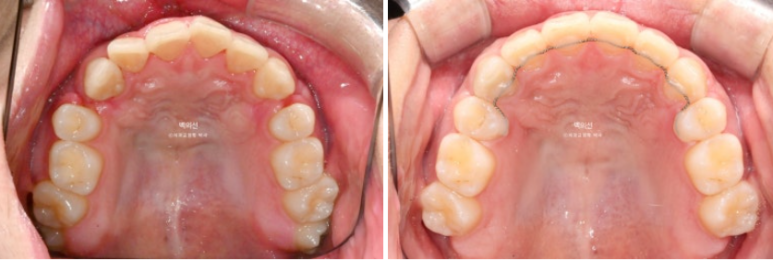

돌출입 수술을 하면 수술 테크닉적으로 작은어금니가 있던 공간이 약 2mm 이상이 남게 됩니다.

송곳니 뒤쪽에 2mm 의 공간이 각각 남았습니다.

이렇게 애매하게 남은 공간을 앞니 배열을 위한 공간으로 사용하는 것이 돌출입 수술교정의 핵심입니다.

이 정도의 남은 공간은 14개의 장치 안에서 해결 가능하기에 인비절라인 라이트로 충분합니다.

전 후 비교 보겠습니다.

24.10~25.08

남아있던 공간은 추가장치로 깔끔히 없어졌습니다.